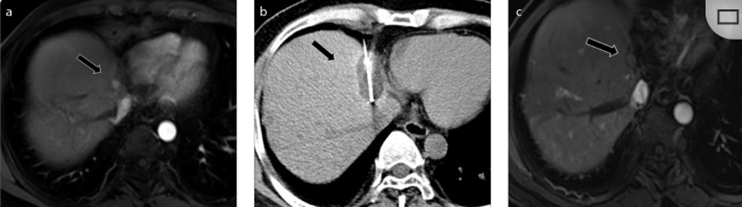

CT引導(dǎo)的冷凍消融

(b) 冷凍消融術(shù)中影像顯示冰球完全覆蓋病變。(c) 19個月后隨訪,沒有發(fā)生局部腫瘤進展。完全消融率為97%(66/68);2名患者均接受了額外的冷凍消融,隨后實現(xiàn)完全消融。平均隨訪期為 12.8 個月(范圍:3-27 個月)。所有患者均接受影像復(fù)查(CT 或 MRI)。11個病灶(16.2%)檢測到局部腫瘤進展,6、12和18個月時的累積局部腫瘤進展率分別為4%、8.2%和20.5%。8例出現(xiàn)遠(yuǎn)處肝內(nèi)或肝外病變的患者接受經(jīng)動脈化療栓塞、經(jīng)動脈化療栓塞加射頻消融治療或全身化療。

主要和次要并發(fā)癥發(fā)生率分別為3.5%(2/57)和22.8%(13/57)。并發(fā)癥主要表現(xiàn)為局部皮膚凍傷、中度氣胸、發(fā)熱,僅有少數(shù)患者接受治療,多數(shù)患者自行恢復(fù)。所有患者能耐受圍手術(shù)期疼痛,VAS 評分范圍在 1-3 分之間(平均 1.65分)。3例患者術(shù)后疼痛加重,VAS評分達(dá)到4~5分,患者口服止痛藥后逐漸緩解。所有患者術(shù)后1天血常規(guī)、白細(xì)胞計數(shù)均升高,血小板均有不同程度下降,但變化值均在正常范圍內(nèi)。肝功能1個月后逐漸恢復(fù)到正常水平。